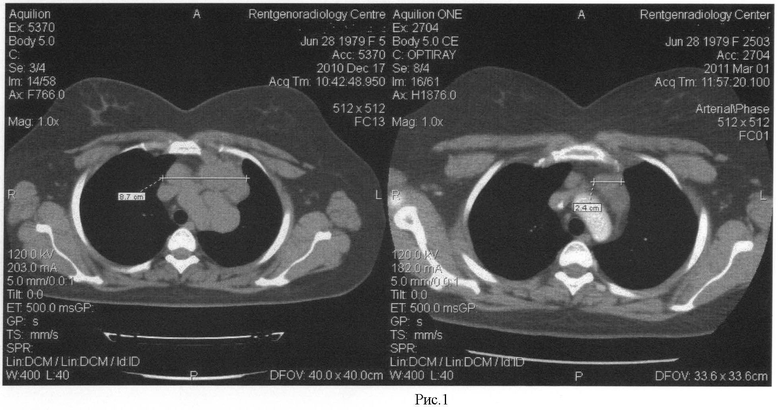

Диагностика лимфомы Ходжкина с помощью ПЭТ и КТ